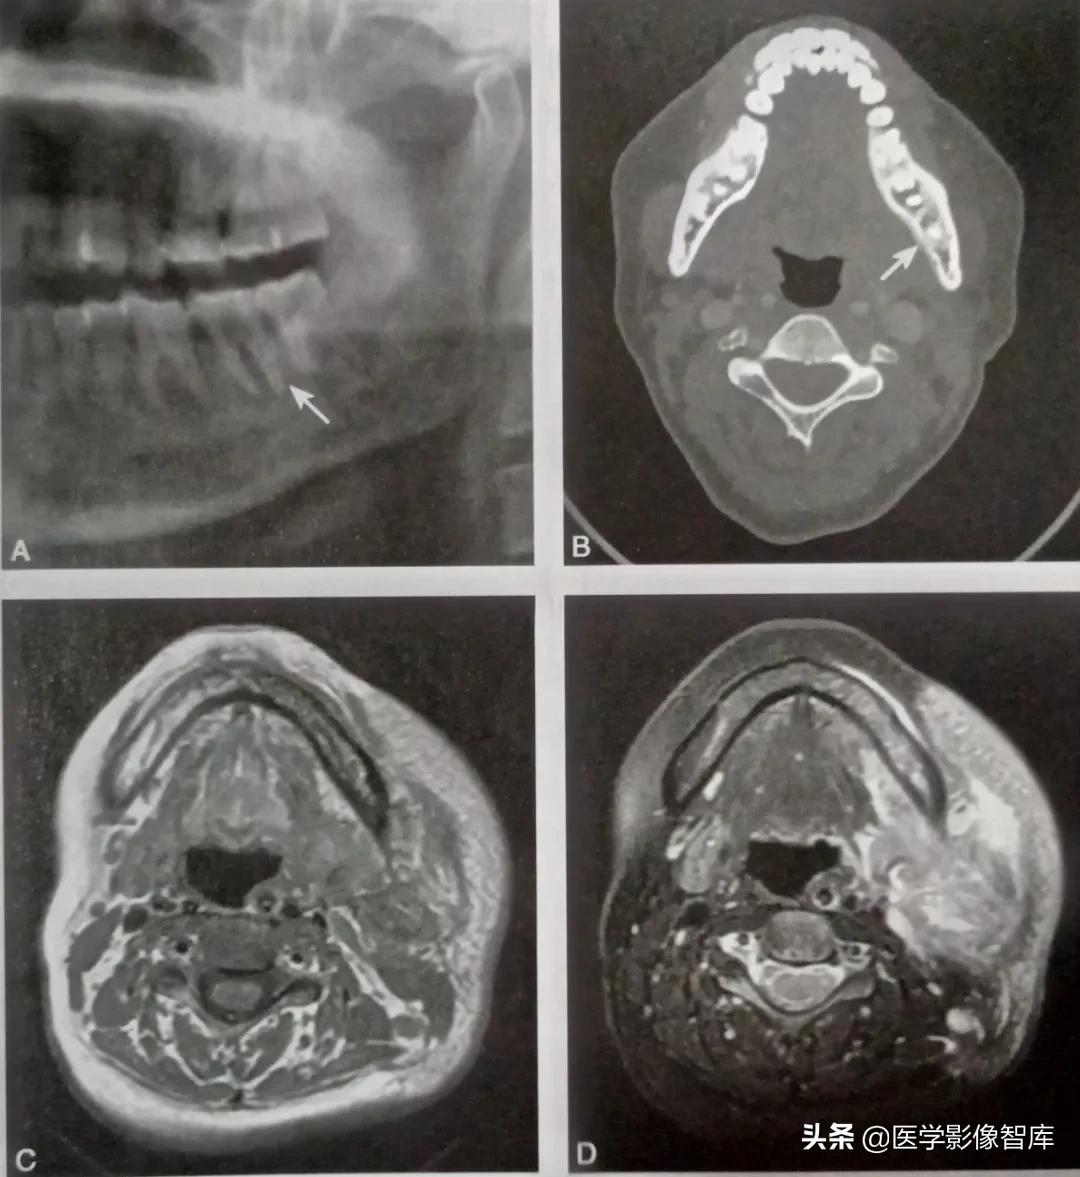

患者,男,52岁。左下颌后牙区肿痛伴麻木5个月,流脓2个月。诊断为左下颌骨化脓性骨髓炎,见图1

图1 左下颌骨化脓性骨髓炎

全景片提示左下7牙根周围骨质密度降低(箭头:A),CT骨窗显示左下颌骨体部舌侧层状骨膜反应(箭头:B)。MRI显示左侧下颌骨骨髓腔信号改变,T1WI呈稍低信号(C),脂肪和制T2WI呈不均匀高信号,周围软组织明显肿胀(D)。